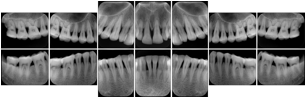

In most standard cases, images are oriented in structured layouts. These structured displays are useful to be shared between providers for reference purposes.

Table OO.1.1-1 shows structured display standard templates, where Viewset ID is based on the Japanese Society for Oral and Maxillofacial Radiology (JSOMR) classification provided by JIRA (Japan Medical Imaging and Radiological Systems Industries Association, www.jira-net.or.jp). Expected or typical teeth to be imaged location, region and designation codes are based on ISO 3950-2010, Dentistry - Designation system for teeth and areas of the oral cavity. For all the hanging protocols listed in OO.1.1-1, the value to use for Hanging Protocol Creator (0072,0008) is "JSOMR" and the value to use for Hanging Protocol Name (0072,0002) does not include "JSOMR" (e.g., "DL-S001A", not "JSOMR DL-S001A").

Table OO.1.1-1. Hanging Protocol Names for Dental Image Layout based on JSOMR classification